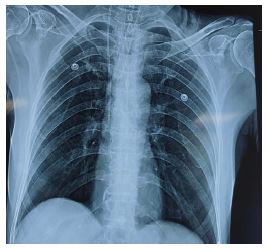

In the postoperative period, the high-sensitivity troponin I level was 779.9 ng/L, well above the normal upper limit of 19 ng/L. Chest X-ray appears normal as shown in (Figure 3).

Figure 3: Chest X-ray of the patient in the postoperative period showing clear lung field.